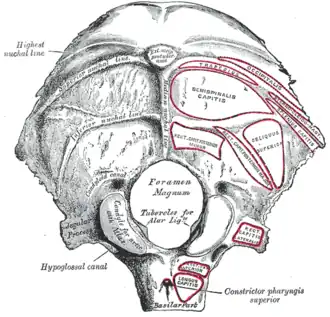

Occipital bone. Outer surface.

Occipital bone. Outer surface. -